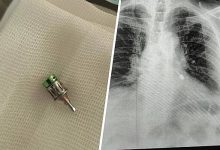

«На консилиуме было принято решение о проведении низкомощностной терапии с радиоактивным йодом-125, — рассказал заведующий отделением онкоурологии ЧОКЦОиЯМ Евгений Киприянов. — Это метод, когда без разрезов через кожу проводится имплантация титановых капсул с радиоактивным веществом в ткань предстательной железы. Точечное излучение помогает эффективному уничтожению опухоли. И контрольное обследование через три месяца показало, что тактика выбрана правильно».